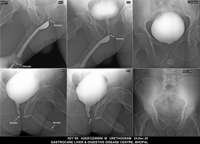

Section: URETHROGRAM Total: 95 images

BaM Enteroclysis Loopogram BaE Fistulogram Urethrogram HSG